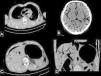

We also noted gas in the internal organs, distributed intravascularly, notably in the brain, heart and liver. Bilateral fluid in the pleural space with the highest volume in the right side was also noted and a higher density was found in the posterior regions, indicating probable hematic components (Figure2).

PMCT images, multiplanar reconstruction axial (A and B) and coronal (C) pulmonary window. Findings in parenchymal organs: A) fluid-fluid level with higher protein decanted in the bilateral pleural space, with a larger volume on the right side; B) gas distributed in intracranial arterial and venous compartments; C) and D) intrahepatic gas in the systemic and portal venous drainage systems (arrows).